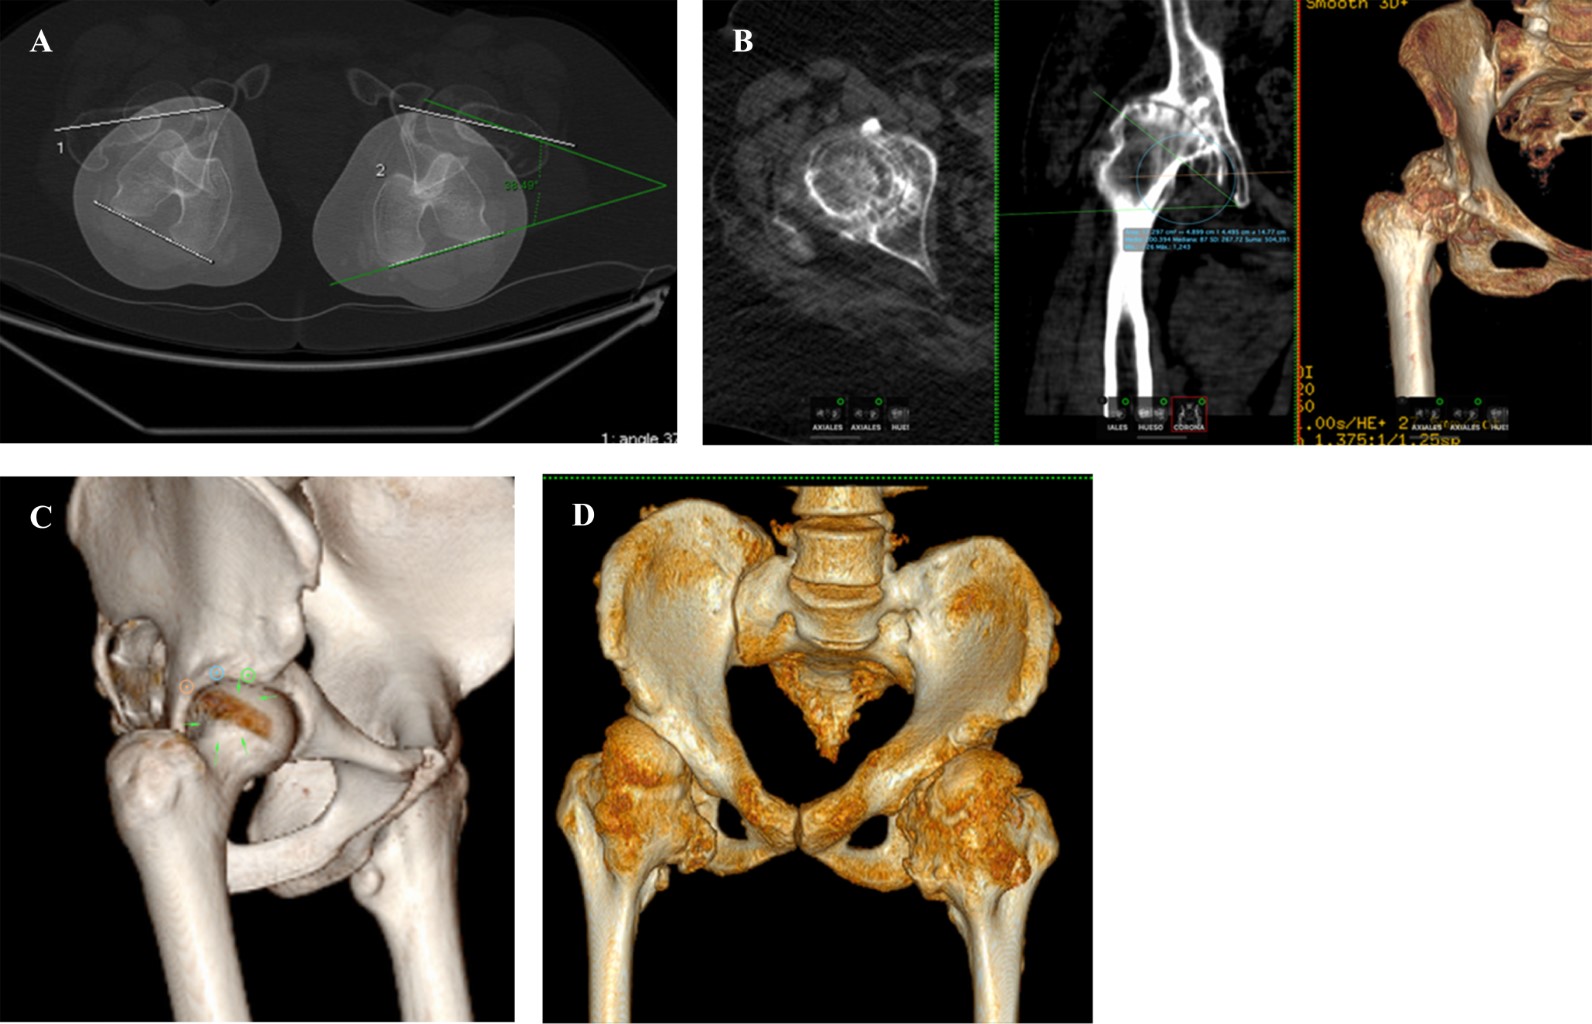

Figure 1

Figure 2

Figure 3

Figure 4

Figure 5

Figure 6

Figure 7

Figure 8

Figure 9

Figure 10

Figure 11

Figure 12

Figure 13

Figure 14